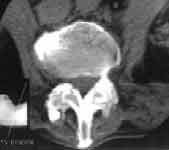

2. Выявляются признаки сакроилеита, т.е. отмечается смазанность субхондрального слоя суставов; вначале незначительно расширение, а затем сужение суставной щели; появляются признаки образования эрозий и остеофитов в суставах позвоночника (Рис. 1.).

Увеличить

Рис. 1. Анкилозирующий спондилоартрит: эрозия в месте прикрепления к позвонку передней продольной связки.